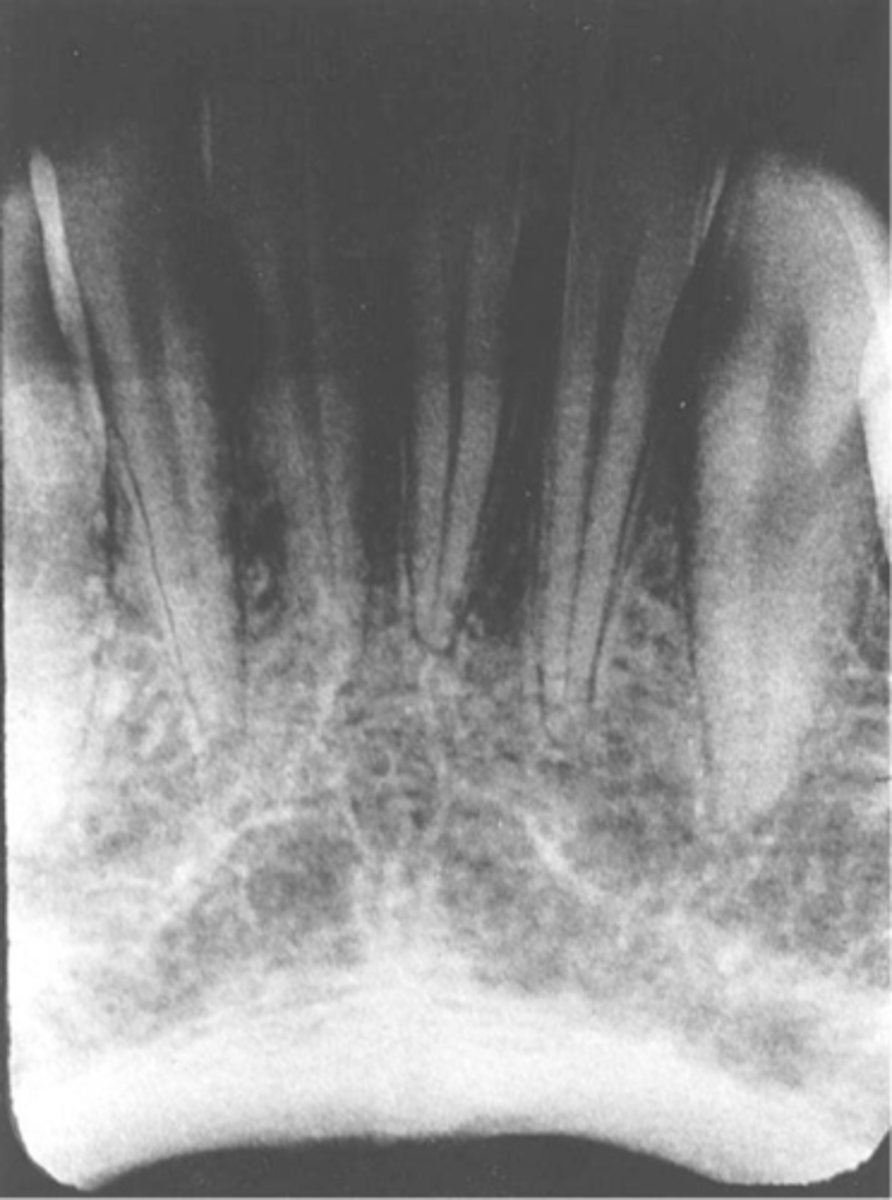

Phalangioma

-Image of the patient's finger is seen

-Error occurs when the finger-holding method is used with the bisecting technique and is not recommended

-To avoid make certain that the patient's finger used to stabilize the receptor is placed behind the receptor and not in front of it

Misc. errors-->Artifacts

-Glasses, Phalangioma, Dentures, lead apron or thyroid collar